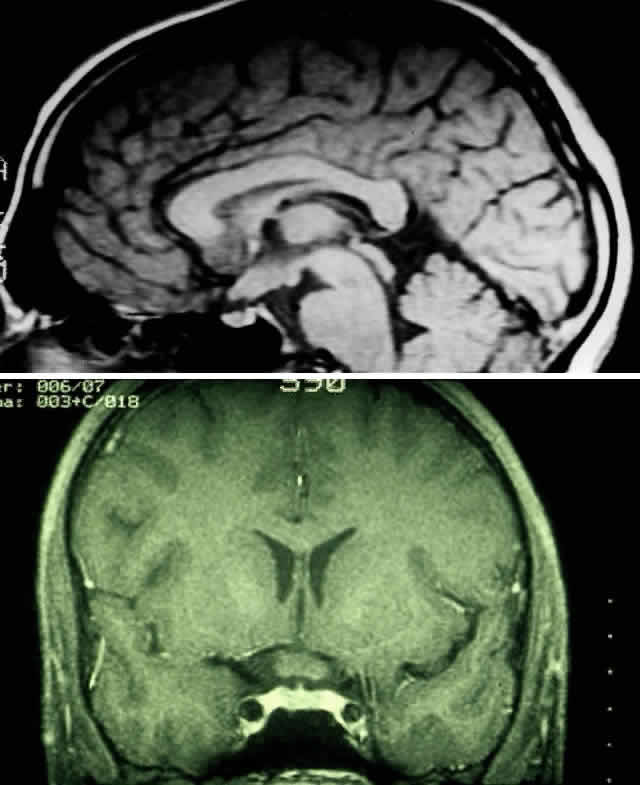

The use of chemotherapy for optic gliomas was prompted by the reported toxicity of radiation to the developing nervous system. Children irradiated before age 5 may have a tendency to incur behavioral and cognitive impairment.122 Results of chemotherapy for optic gliomas are difficult to interpret because of the sometimes indolent nature of these lesions, variably reported study follow-up periods, and small sample sizes. It does appear, however, that chemotherapy can effectively postpone radiation122 (Fig. 11 A and B). Unfortunately, there is little evidence that chemotherapy can provide long-term control of these tumors.20,122 In one series, approximately 60% of children treated for gliomas of the hypothalamus and optic pathways eventually had a relapse.122

Fig. 11. MRI scans demonstrating optic pathway glioma in a 14-month-old child with neurofibromatosis type 1, who presented with irritability and bilateral visual loss. The patient was treated with two courses of carboplatin and vincristine, resulting in marked visual recovery and a reduction in tumor size. Compare pretreatment MRI scan (A) with post-treatment MRI performed 5 months later (B). (Courtesy of Russell W. Walker, MD)